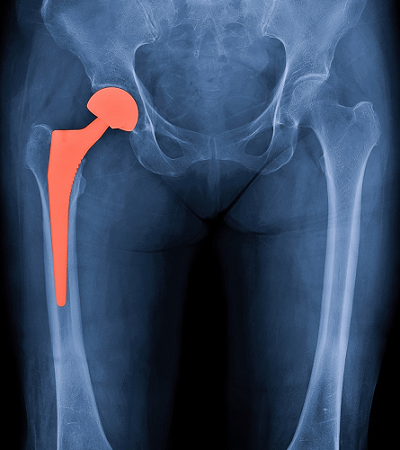

She needs a hip replacement. She is frightened about going into surgery.

We told you that it was an ongoing hip problem and that she needed hip replacement surgery.

Madonna is 62 years old, which puts her in the right age group of those that are more likely to need a hip replacement.

The bandage is covering the bulk of the scar, but the placement of the scar indicates a hip replacement.

There are some who might look at Madonna’s scar and think that it doesn’t look like the scars they have seen on other hip replacement patients.

There are actually several different types of hip replacement surgery (e.g. partial hip replacement, hip resurfacing) and several different approaches by surgeons (e.g. anterior, lateral, posterior) that affect scar location and scar length. Some surgeons can even do an anterior approach where the scar is hidden in your bikini line!

Based solely on the scar, Madonna appears to have had an anterior or lateral interior hip replacement surgery.